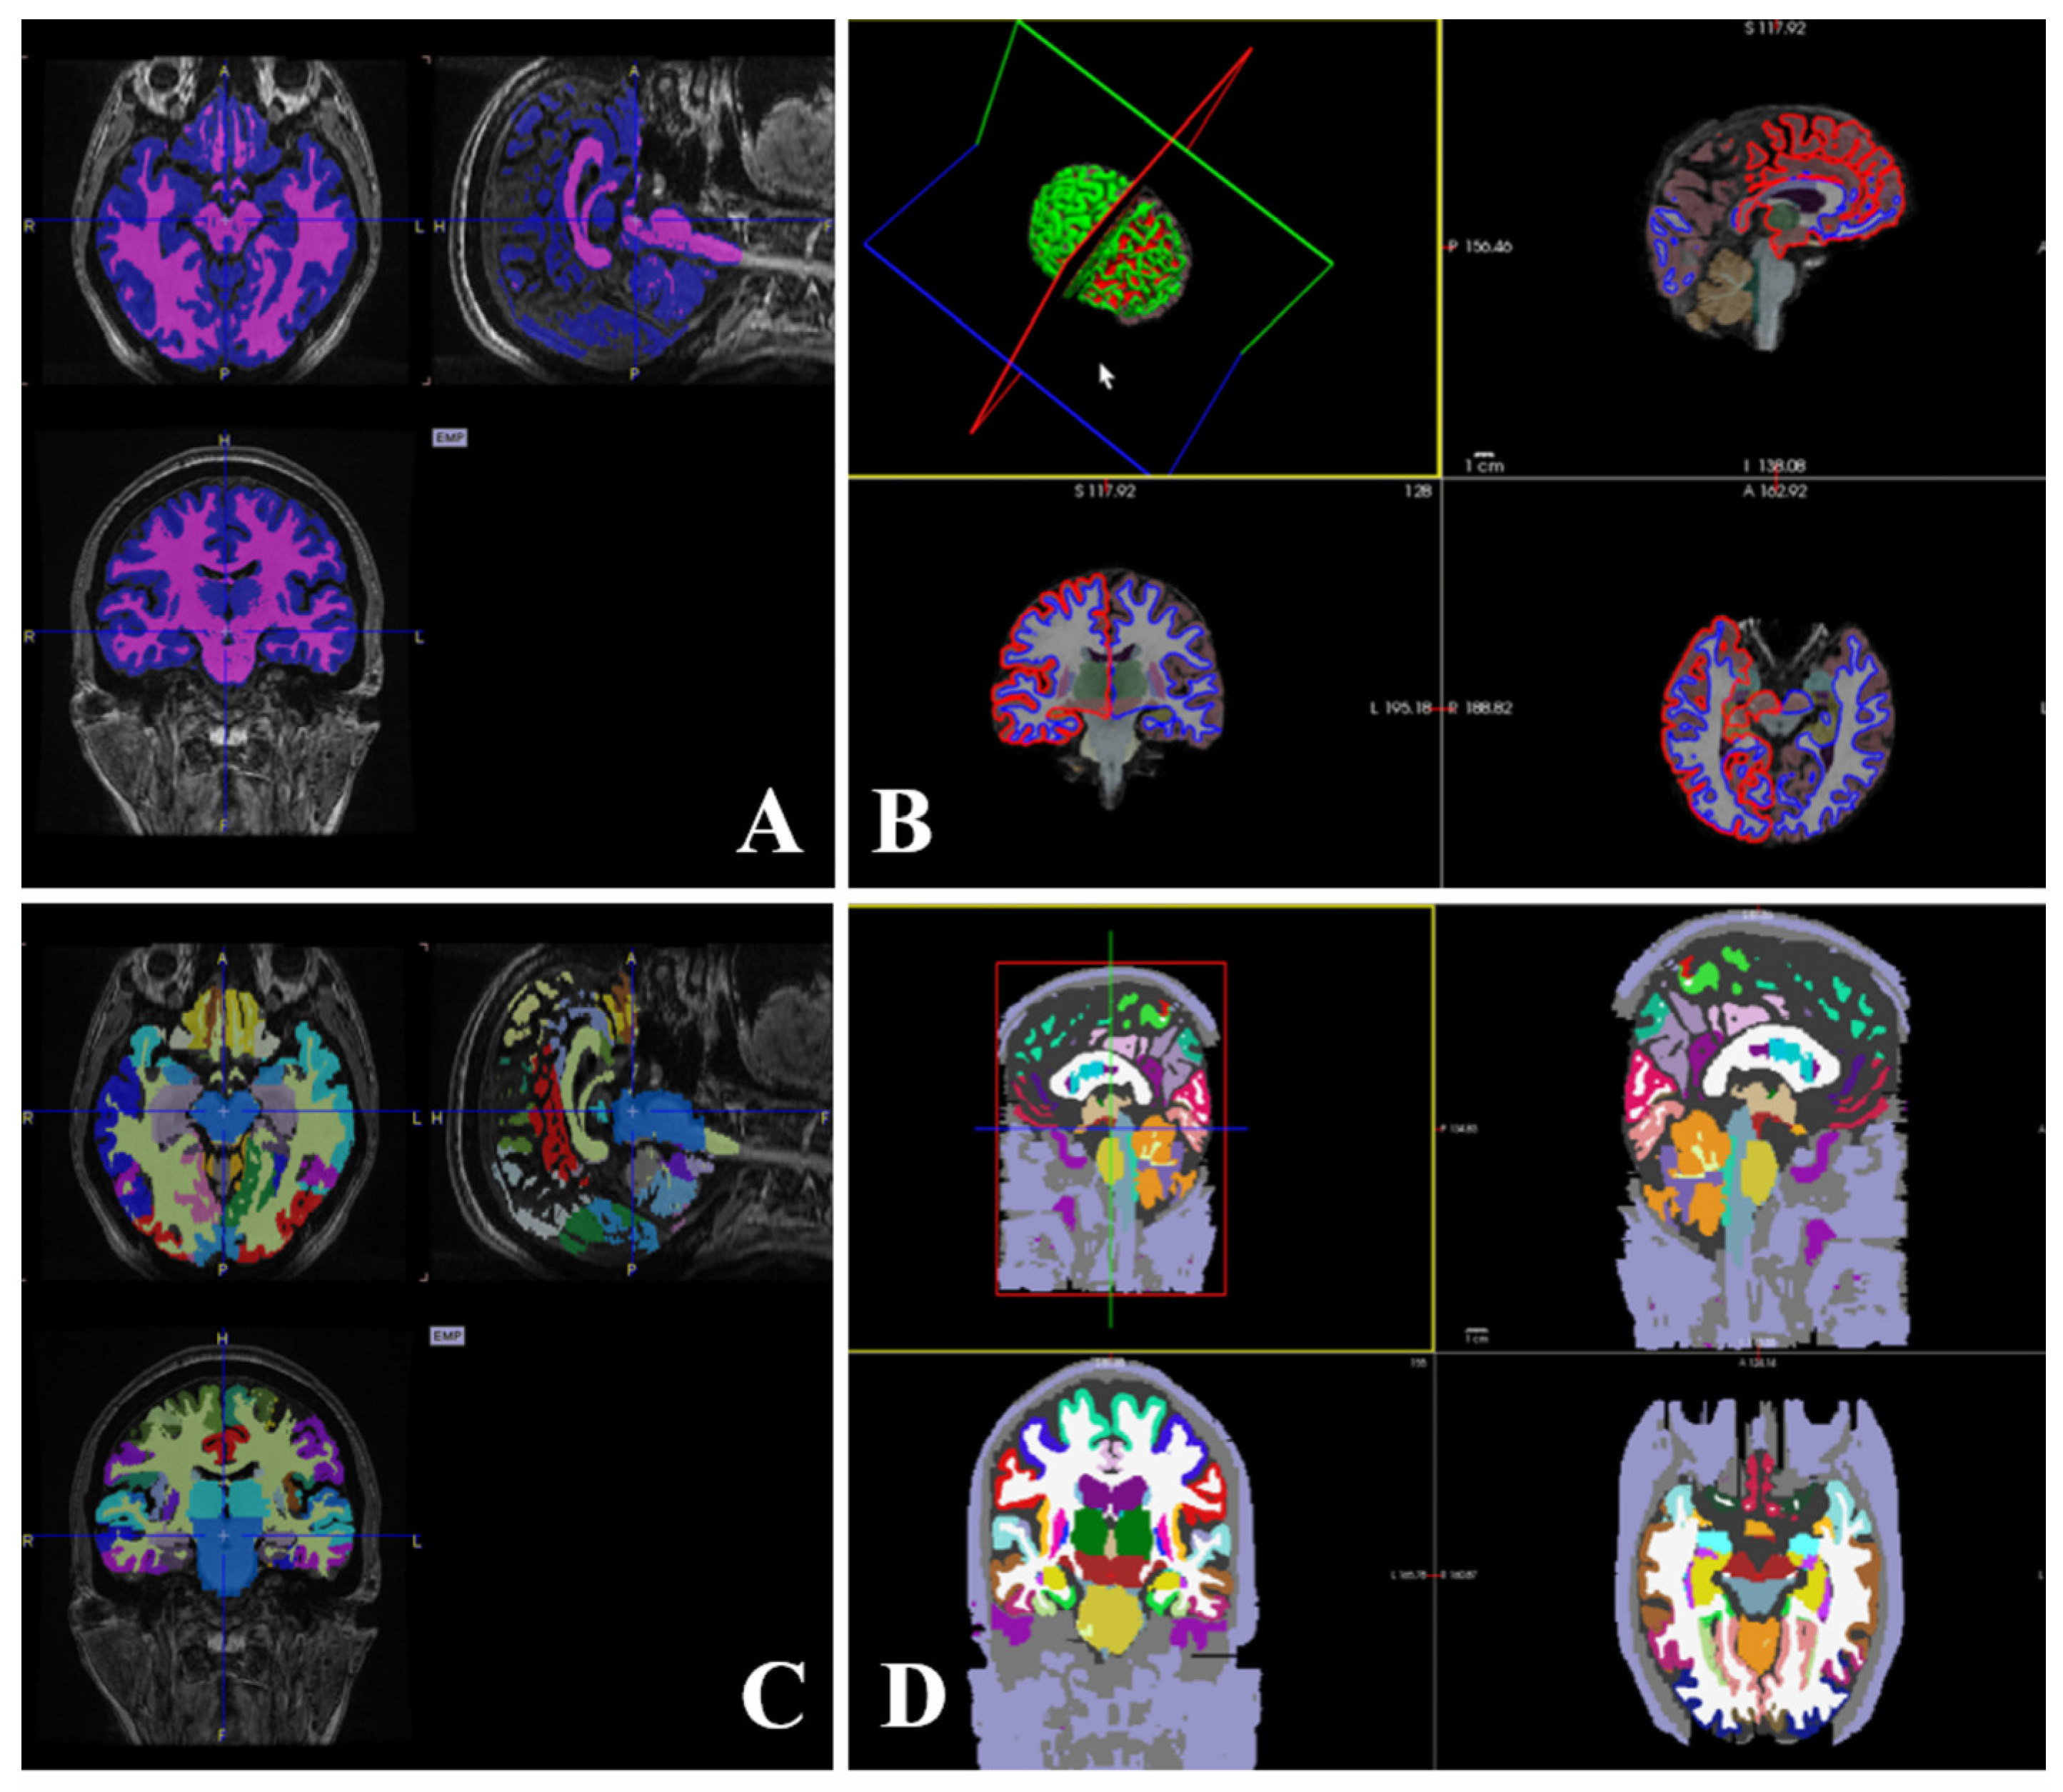

Parcellation and segmentation images by MRI contrast are presented in individual spaces overlaid on the MRI, as shown in Figure 2. To extract the SUV values, brain PET, parcellation, and segment images were co-registered using SPM. For parcellation images extracted by the PMOD algorithm, the SUV was calculated in the region of the AAL atlas, and parcellation images extracted by the FreeSurfer algorithm were used to find the SUV in the region of the Desikan-Killany atlas. These two atlases may differ slightly in the cortical and subcortical regions. Figure 2 illustrates the regions of the AAL atlas in the PMOD viewer, and the regions of the Desikan-Killany atlas in Freeview.

As shown in Figure 2, cropping was performed using PMOD for the PET images and T1-weighted MRI to reduce the computation time. After re-slicing individual images of the subject using SPM, co-registration was performed on cropped T1-weighted MRI. Re-slicing of brain PET, parcellation, and segmentation were performed to match the resolution of T1-weighted MRI. After T1-weighted MRI was processed for skull stripping and intensity normalization, the regions were determined by registration to the atlas. SUV were extracted from regions where brain parcellation and segment images in the MRI space overlapped the brain atlas. For the brain atlas, SUV data were extracted using the AAL atlas in PMOD and Desikan-Killiany atlas in FreeSurfer.

Figure 2. Representation of parcellation and segmentation images using PMOD (A), cortical parcellation, and sub-cortical segmentation images using FreeSurfer (B), AAL atlas (C), and Desikan-Killiany atlas (D).